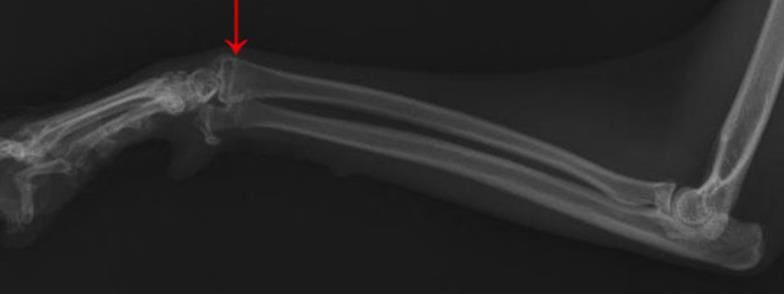

나이가 어린 학생들은 뼈가 생성되면서 관절 사이에 얇은 원판이 만들어지게 되는데 그것이 성장판이라 합니다. 이것이 열렸는지 닫혔는지에 따라 키가 결정되는 만큼 그 시기를 상시적으로 체크하는 것이 중요합니다. 가장 좋은 것은 병원에 방문하여 확인하는 것이지만 비용 혹은 시간적인 여유 때문에 어렵습니다. 그래서 지금 소개해드리는 자가진단을 자주 시행하는 것을 추천드립니다.

무릎뼈 확인

먼저 발이 닿지 않는 의자에 앉은 후 무릎뼈를 꾸욱 눌러보시길 바랍니다. 이때 무릎뼈와 다리 사이에 있는 연골의 있어 헷갈릴 수 있는 만큼 예민하게 살펴보시길 바랍니다.

만약 성장판이 닫힌 어른의 경우라면 말랑거리고 안으로 들어가지만 그렇지 않은 아이의 경우 조금 다른데요. 약간의 딱딱함이 느껴진다면 성장판이 아직까지 열려 있다고 생각하실 수 있습니다.